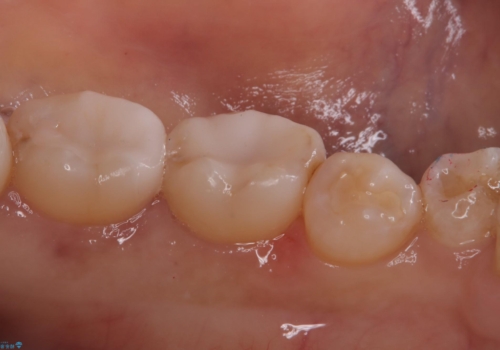

- 主訴:詰め物が外れた これを機に白い詰め物にやり替えたい

左下7番目の歯の詰め物が外れ、セラミックインレーでのやり替えとなりました。

隣在歯にも保険適用もメタルインレーが入っており、咬合面のインレーと歯質の境目が虫歯になっていたこともあり、合わせてのやり替えとなりました。

左下7番めの歯、フロスを通したらインレーが外れてしまったとのことで、適合具合の精密さや、これを機に白い詰め物にしたいとのことからセラミックインレーでのやり替えとなりました。

また、6番目の歯にも保険適用のメタルインレーが入っており、咬合面インレーと歯質境目にう蝕を認め合わせてのやり替えとなりました。